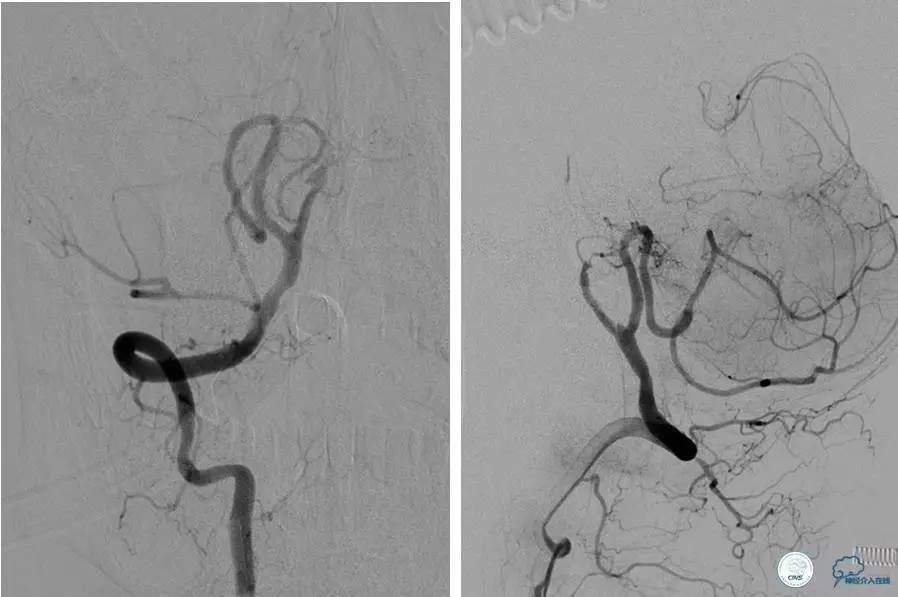

病例4

患者:53岁男性,反复脑梗死3个月。

▼给予球囊扩张成形,闭塞段较长,决定药物治疗视察,二期再给予支架治疗。

▼药物治疗1个月,再次发作。再次来我院支架治疗。

▼支架术后,效果好。

因此,某些患者分期治疗也具有合理性。